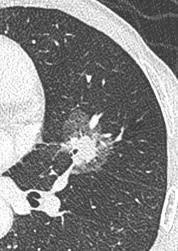

抽烟者所发生的肺部结节,大部分是实性肺结节;

不吸烟者所发生的肺部结节,大部分是磨玻璃肺结节。

这两种肺部结节性质完全不同。

实性肺部结节,如符合手术指正,需尽早进行手术切除,而且越早越好,因为像“老烟鬼”所患的这种实性肺部结节,它增长速度非常快,可能在一年内就迅速变为中晚期肺癌。

实性结节

结节长相:肺内圆形或类圆形密度增高影,病变密度足以掩盖其中走行的血管和支气管。

产生原因:一般实性肺结节恶性可能性很高,多是由肿瘤导致。但是否是恶性,还需要结合大小等因素综合判断。